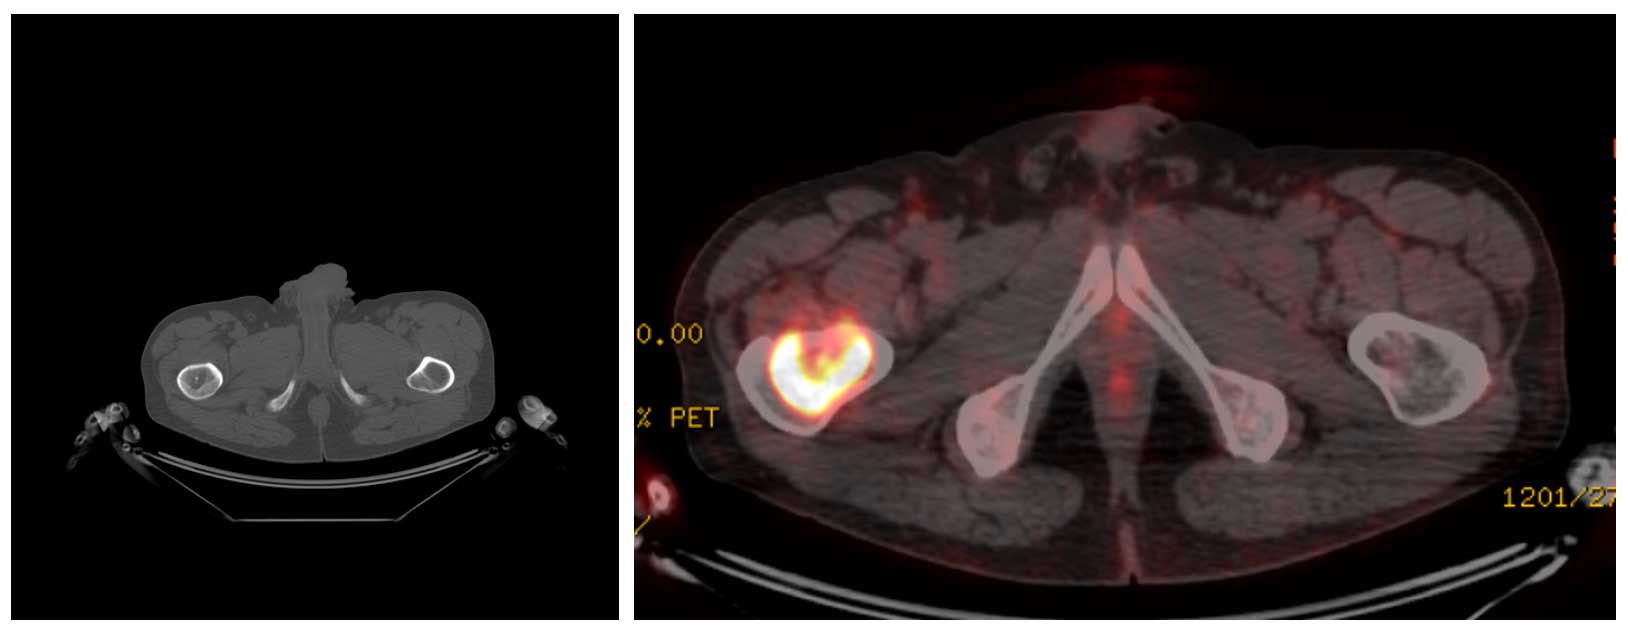

Ameliyat Öncesi: PET-CT’de kıkırdak içerik ve artmış aktivite görülmekte.